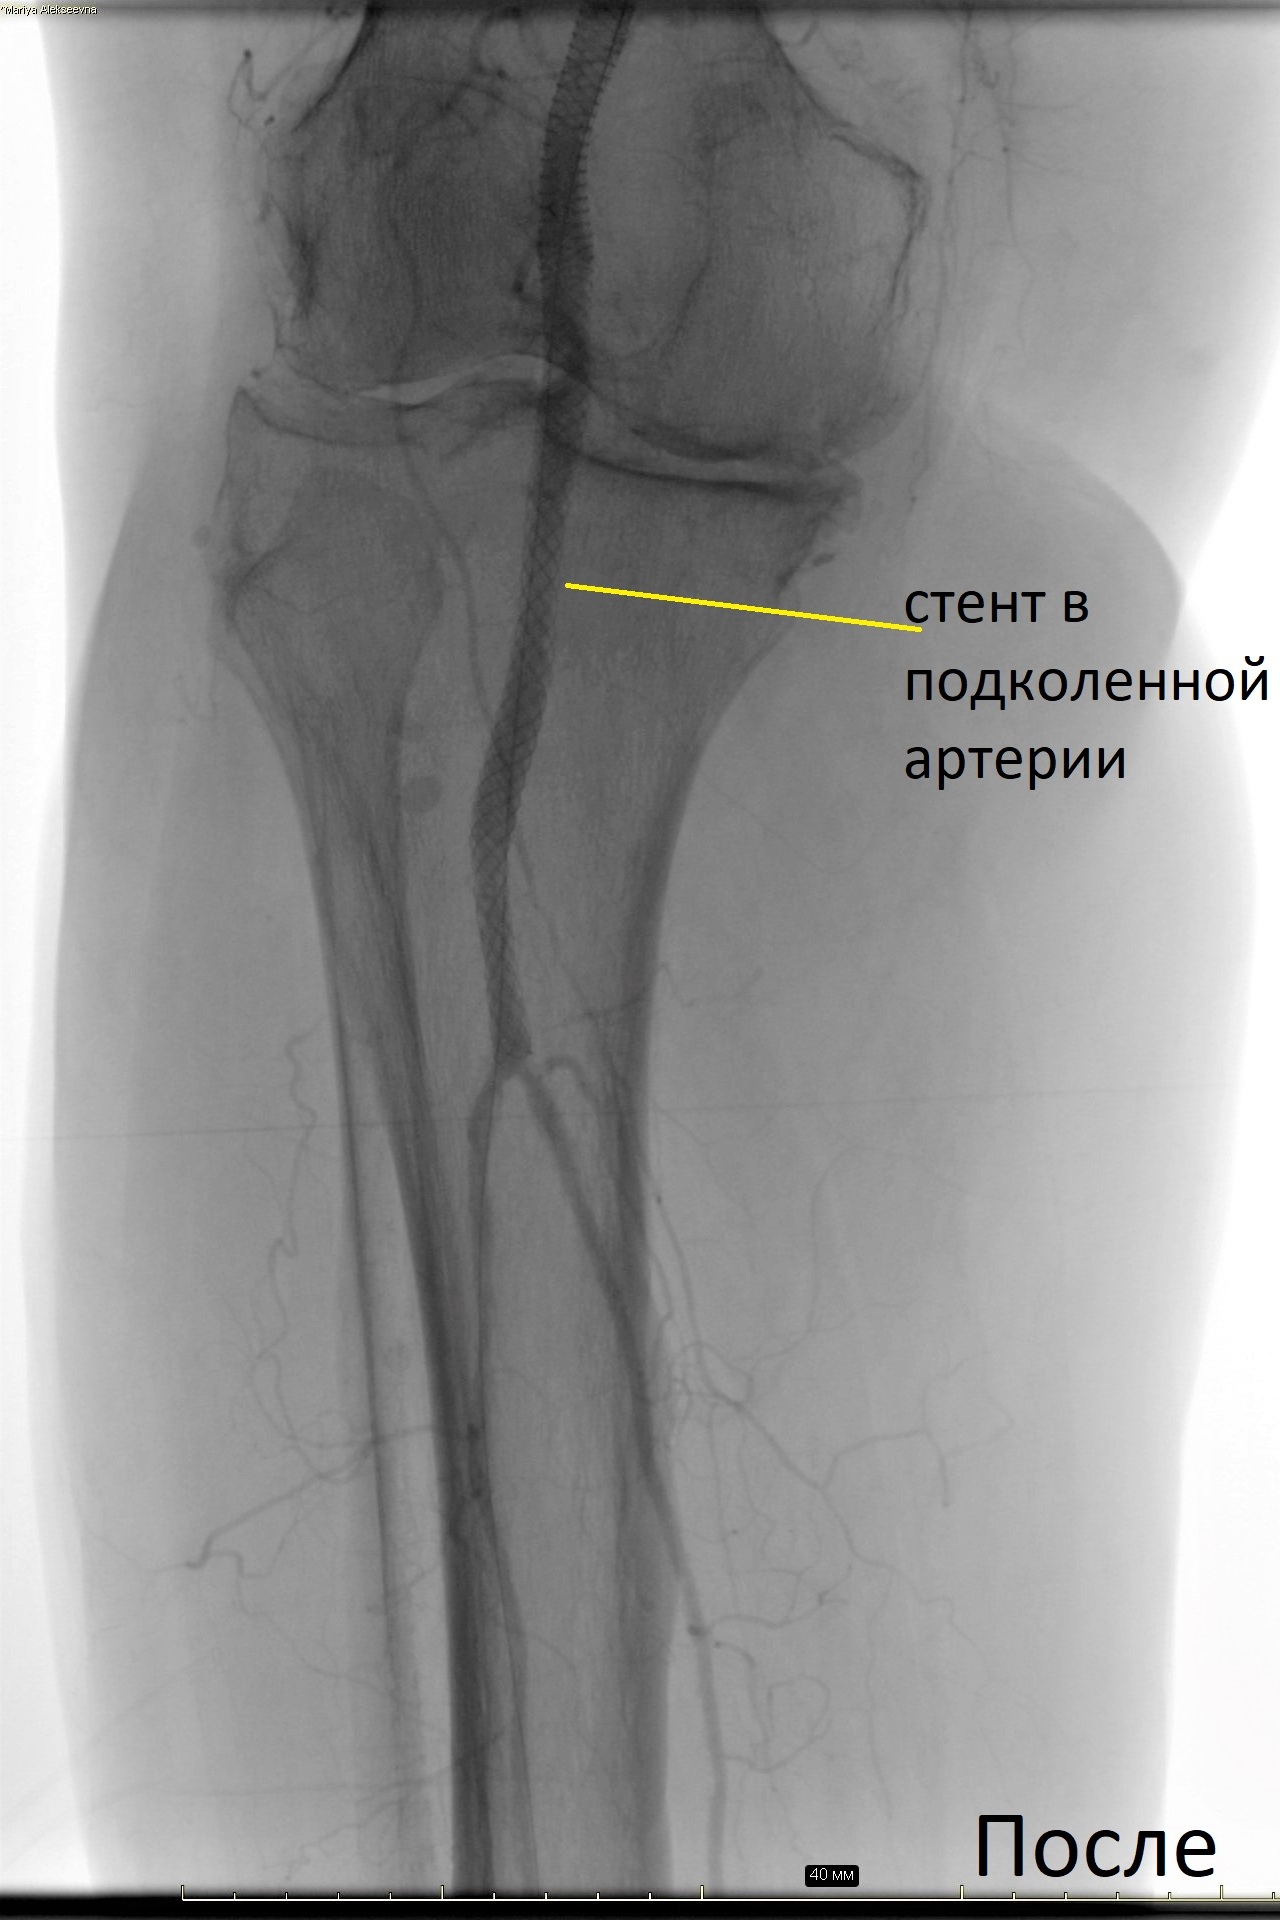

Центр Алмазова является уникальным учреждением, в котором в повседневную клиническую практику интегрированы мультидисциплинарный подход и персонифицированная медицина, основанные на сотрудничестве и взаимодействии медицинских специалистов смежных дисциплин. Уже 6 месяцев на базе клиники сосудистой хирургии учреждения успешно работает команда профессионалов, оказывающая высокотехнологичную помощь больным с диабетической стопой с применением в лечебном процессе инновационных малоинвазивных и гибридных технологий, в том числе эндоваскулярной реваскуляризации артериального русла.

Благодаря ежедневной слаженной работе команды сосудистых хирургов, кардиологов, эндокринологов и травматолога-ортопеда, удалось избежать больших ампутаций, а значит, и серьезной инвалидизации этих пациентов, добиться заживления трофических язв, восстановления двигательных функций. Все больные смогли вернуться к привычному образу жизни. После выписки они находятся под динамическим наблюдением специалистов учреждения.

Залогом успеха в лечении этой категории больных является выстраивание индивидуальной стратегии, включающей такие этапы, как реваскуляризация артериального русла, коррекция сахарного диабета, рациональная антибактериальная терапия, костно-пластическая реконструкция, а также лечение других осложнений сахарного диабета. Только при соблюдении всех этих принципов удается добиться результата, к которому стремится каждый специалист большой команды Центра Алмазова.